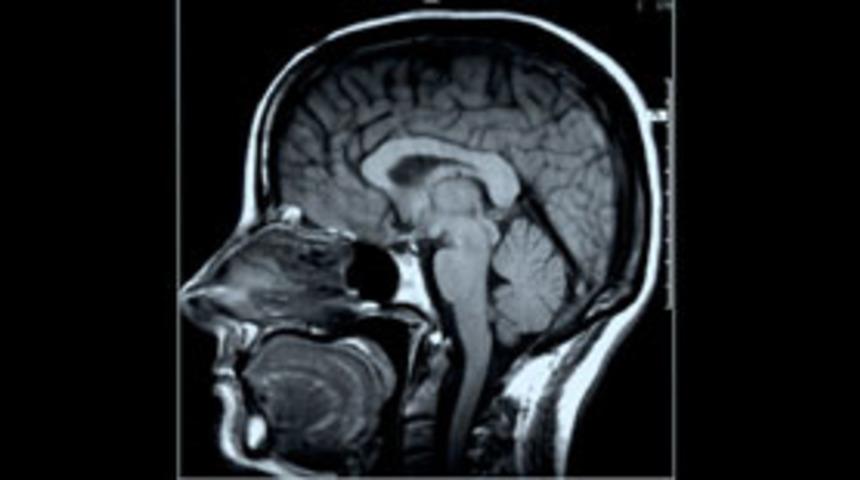

Kanada'da yapılan bir araştırmaya göre, dini meditasyon sırasında, bazı bilim adamlarının savunduğu gibi beynin sadece bir kısmının değil, birçok bölgesinin harekete geçtiği belirlendi.

Montreal Üniversitesi Psikoloji Bölümü'nden Dr. Mario Beauregard ve ekibi tarafından yürütülen araştırmada, 23 ila 64 yaşındaki 15 rahibenin dini meditasyon sırasında beyin faaliyetleri MRI (manyetik rezonansla görüntüleme tekniği) ile incelendi. Sonuçları bu hafta "Neuroscience letters" adlı dergide de yayınlanacak araştırmada, bazı bilim adamlarınca 10 yıl kadar önce dile getirilen ve beynin ön tarafında dini inanışı yöneten "Tanrı noktası" adlı özel bir bölgenin bulunduğu teorisinin sorgulanması amaçlandı.

Dr. Beauregard ve ekibi tarafından yürütülen araştırma, dini ibadete odaklanma sırasında, beynin faaliyetinin sadece "ön lob" ile sınırlı kalmadığını ortaya çıkardı.

Araştırmasının sonuçlarını yorumlayan Dr. Beauregard, "Beyinde tek başına bir Tanrı noktası bulunmuyor. Bu tip faaliyet sırasında, duygulanma, benlik bilinci veya vücudu boşlukta betimleme gibi değişik fonksiyonlarla birlikte tüm beyin çapında karmaşık bir hareket söz konusu" diye konuştu.Deneyleri sırasında, rahibelerin kendilerine "Tanrı ile birlikte bir mutluluk ve barış duygusu" hissettiklerini anlattıklarını söyleyen Beauregard, bu sırada özellikle beynin heyecan kısmı olan limbik sistem bölgesinde bir hareketlenme tespit ettiklerini kaydetti.

İncelemeleri sırasında ayrıca vücudun betimlenmesine bağlı bir bölge olan yan kortekste de değişiklik belirlediklerini anlatan Beauregard, din adamlarının meditasyon sırasında vücutlarını daha az hissettiklerini söylemelerinden ötürü beynin bu bölümünün önemli olduğunu belirtti. Kanadalı bilim adamı buna karşın, bu faaliyet sırasında beyin dalgaları seviyesinde bir yavaşlama tespit ettiklerini belirterek, "Beyin dalgalarını isteğe bağlı olarak yavaşlatmak olanak dışı. Bu durum bize dini meditasyon

sırasında elektrik seviyesinde beynin çalışmasında bir değişiklik olduğunu gösteriyor" dedi.